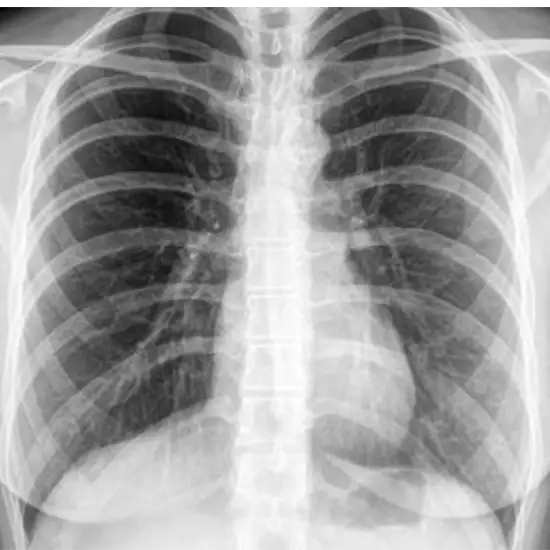

X-ray Left SI Joint Oblique

X-rays of the sacroiliac joints are a safe and painless way to see the spine area that joins with the pelvis (hip bones) in the lower back.